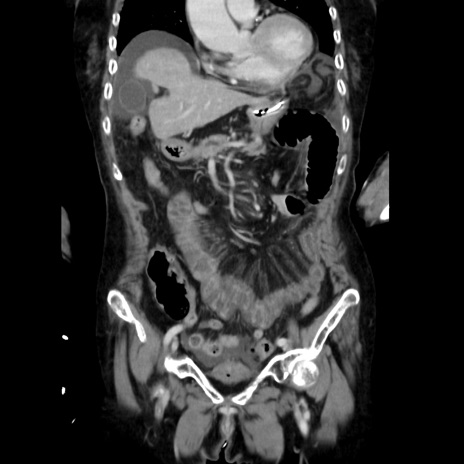

症例40(冠状断像)

【症例】90歳代女性

【主訴】腹痛・嘔吐

【現病歴】 食欲低下、嘔吐があり昨日他院受診。肺炎と診断され入院となる。入院後より腹部全体に圧痛あり。胃管留置され経過みていたが、症状持続するため、

当院転院となる。

【既往歴】胸椎圧迫骨折、胆石症

【身体所見】腹部:中央に激痛あり、圧痛あり、反跳痛不明

【データ】WBC 17100、CRP 18.82

冠状断像